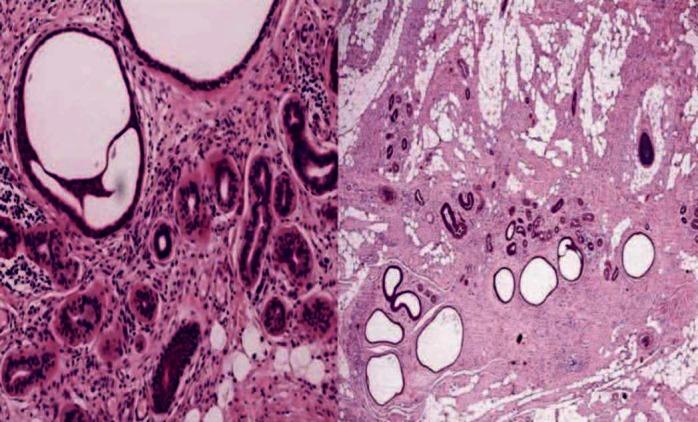

Only a few published case of fibrous hamartoma of infancy (FHI) have commented on the changes in the overlying skin. There are descriptions of individual cases with cutaneous hyperpigmentation, hypertrichosis and hyperhidrosis. It is interesting to describe our case because, to our knowledge, the altered pigmentation of the overlying skin, with hairs on the surface, and eccrine gland hyperplasia combined with abortive hair follicles has not been reported together in association with the FHI. We recommend that all the biopsies must be excisional including overlying skin, thus the epidermal and dermal adnexal changes can be assessed in the microscopic evaluation which could have relevant implications from clinical and embryological point of view.

仅有少数已发表的婴儿纤维性错构瘤(FHI)病例提及了其上方皮肤的变化。有个别病例出现皮肤色素沉着、多毛症和多汗症的描述。描述我们的病例很有意思,因为据我们所知,FHI合并上方皮肤色素改变、表面有毛发以及小汗腺增生伴毛囊发育不全的情况尚未见一同报道。我们建议所有活检均须完整切除包括上方皮肤,这样在显微镜评估中就能对表皮和皮肤附属器的变化进行评估,这从临床和胚胎学角度可能具有相关意义。